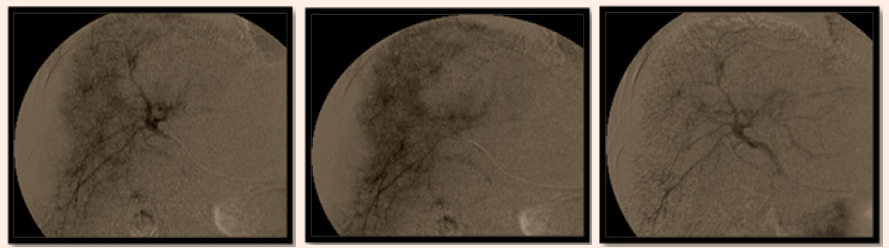

Follow up by triphasic CT after 3 months of combined therapy showing: Good uptake of lipiodol droplet by the residual tumoral tissue with no newly developed lesions. Follow up after three months of combined therapy was showing reduction of the size of the lesion into a hypo-dense non enhanced 3cm area with no residual tumoral reactivity and AFP reached 40IU/DL. After 6months patient developed mild ascites with mild elevation in AFP reaching 90IU/dl with deterioration of the liver function and CT showing no reactivity. After 8months of follow up she developed mild increased in AFP level reaching 110IU/DL then returning to 90IU/DL and a triphasic CT was done revealed no newly developed lesions or reactivity (Figure 4).

Figure 4 Follow up by Triphasic CT after 3 months of combined therapy.

The last triphasic CT was done shows no residual tumoral reactivity and drop in the AFP level: After 12months the patient developed significance elevation in AFP level reaching 565.6mg/ml and triphasic CT showing recurrence of tumoral reactivity that is will treated again by TACE (Figure 5) and Figure 6 shows Triphasic CT after 12months showing recurrence of the tumoral.